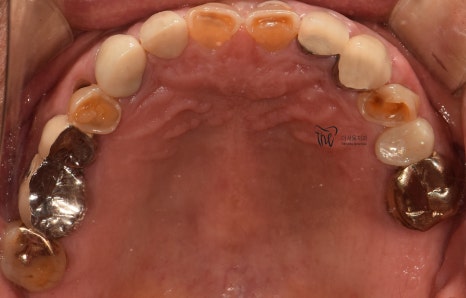

우선 교합면에서 바라보게 되면,

곳곳에 치아 결손 부위가 관찰이 되는데

이가 빠진지 시간이 꽤나 오래 되셨다는 것을

한 눈에 알아차릴 수 있습니다.

바로 결손부위를 보게 되면, 골 폭이 상당히

좁아져 있는 것을 볼 수 있는데 이는 치아 상실 후

방치 된 시간이 꽤나 오래 되었다는 것에 따른

반증이기 때문입니다.